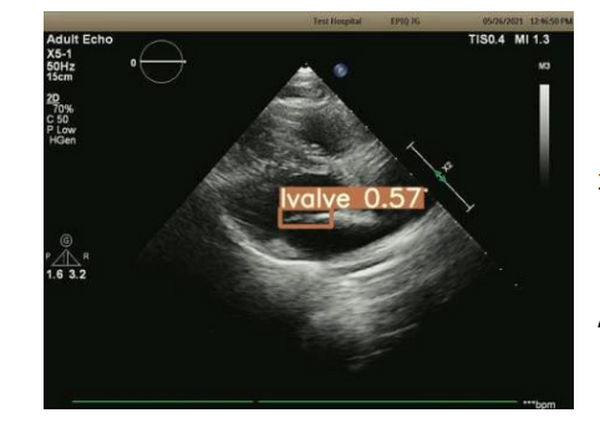

Machine learning – based image processing

超音波プローブの位置や角度に応じて心疾患に特徴的なエコー画像が大きく変わるため、微細なコントロールが不可欠。そこで心疾患のエコー画像をAIに読み込ませ、それらと照合しながら適切なエコー断面を描出するAI基盤技術を開発している。